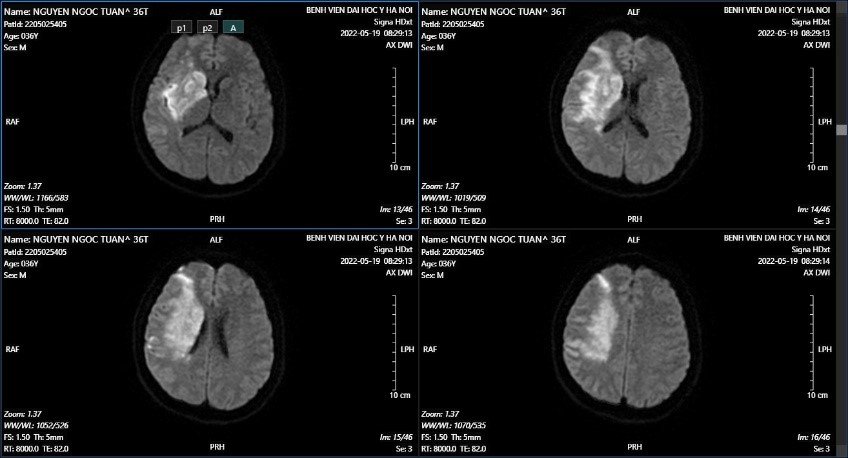

Chụp MRI sọ kiểm tra phát hiện tổn thương nhồi máu não bán cầu não phải.

Hình ảnh MRI sọ (19/05): Tổn thương ở thùy trán, thùy thái dương và thùy đỉnh phải thuộc vùng cấp máu của động mạch não giữa phải, gây hiệu ứng khối nhiều xung quanh. Trên chuỗi xung mạch TOF, động mạch cảnh trong phải nhỏ, bị đè ép bởi khối u, không thấy tín hiệu dòng chảy ở đoạn siphon động mạch cảnh trong, động mạch não giữa phải đoạn M1 nhỏ, các đoạn còn lại động mạch não giữa không thấy hẹp tắc.